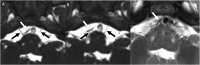

Figure. Comparison of constructive interference in steady state and conventional T2 MRI of the ventral brainstem

Two consecutive constructive interference in steady state (CISS) images (A, B) clearly show cranial nerve (CN) VI bilaterally (black arrows) and the course of the right anterior inferior cerebellar artery (AICA) (white arrows), while the relationship between the R AICA and R CN VI is not visualized by conventional T2-weighted imaging (C).